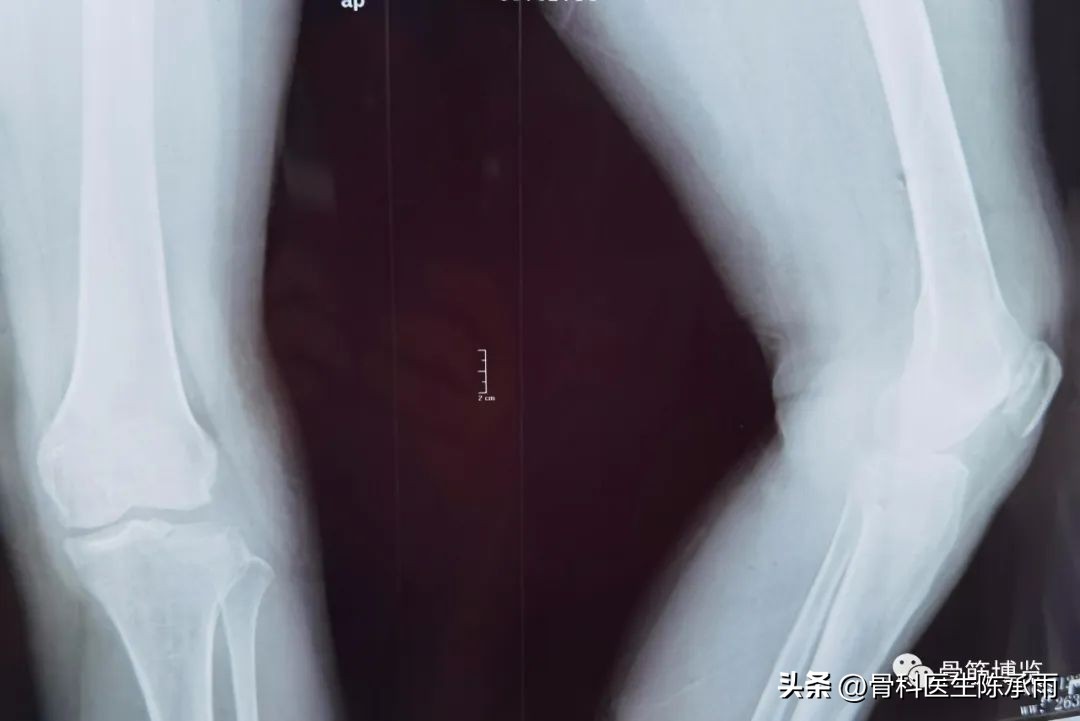

1例

2例

3例

4例

5例

6例

7例